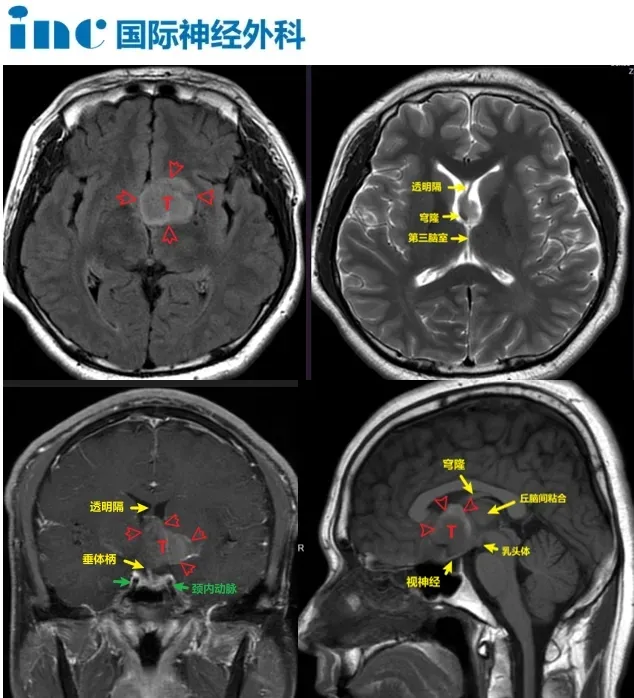

陆先生术前影像

陆先生寻求到INC国际神经外科医生集团旗下INC世界神经外科顾问团(WANG)的巴朗特菲教授进行手术。“一切都交给巴教授了,非常有幸遇到巴教授!”陆先生术前谈话时表示,坚定选择手术的信心来源是对于巴教授的信任。